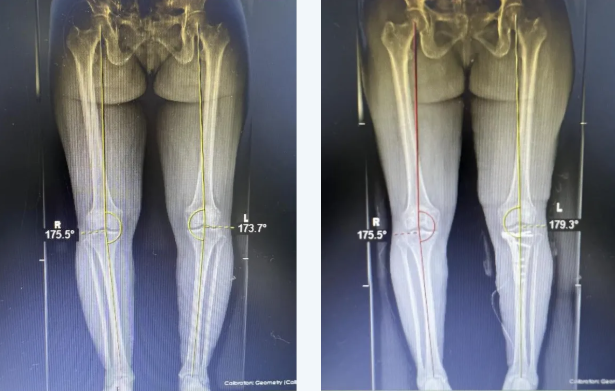

患者代某某,女,56 岁,因「右膝关节反复疼痛 4 年余,加重伴畸形 2 年余」家属陪同就诊骨关节科。骨关节科团队在详细评估患者病情后,决定为其实施 APTT-HTO(胫骨结节中腘肌前-胫骨高位截骨)矫形保膝手术。手术由骨关节科吴相阳主任医师主刀,在麻醉科、手术室等多科室的紧密配合下,顺利完成。

骨关节科团队率先在重庆地区完成 APTT-HTO(胫骨结节中腘肌前—胫骨高位截骨)矫形保膝手术,标志着我院骨关节科在关节外科领域取得重大突破,为膝关节骨性关节炎患者带来了更高效、创伤更小的手术治疗选择。它通过在胫骨高位进行截骨,矫正下肢力线,将膝关节负荷从磨损严重的内侧间室转移至相对正常的外侧间室,从而缓解疼痛,改善关节功能,延缓关节退变,促进关节软骨再生,为膝关节骨性关节炎患者提供了一种新的治疗选择,特别是对渝东南片区人民群众是更好的治疗方法,让他们迅速摆脱膝关节骨性关节炎疼痛和功能障碍的痛苦折磨,更好地恢复健康,回归社会生活。同时,这也将进一步推动我院骨关节科的发展,提升医院的整体医疗水平。